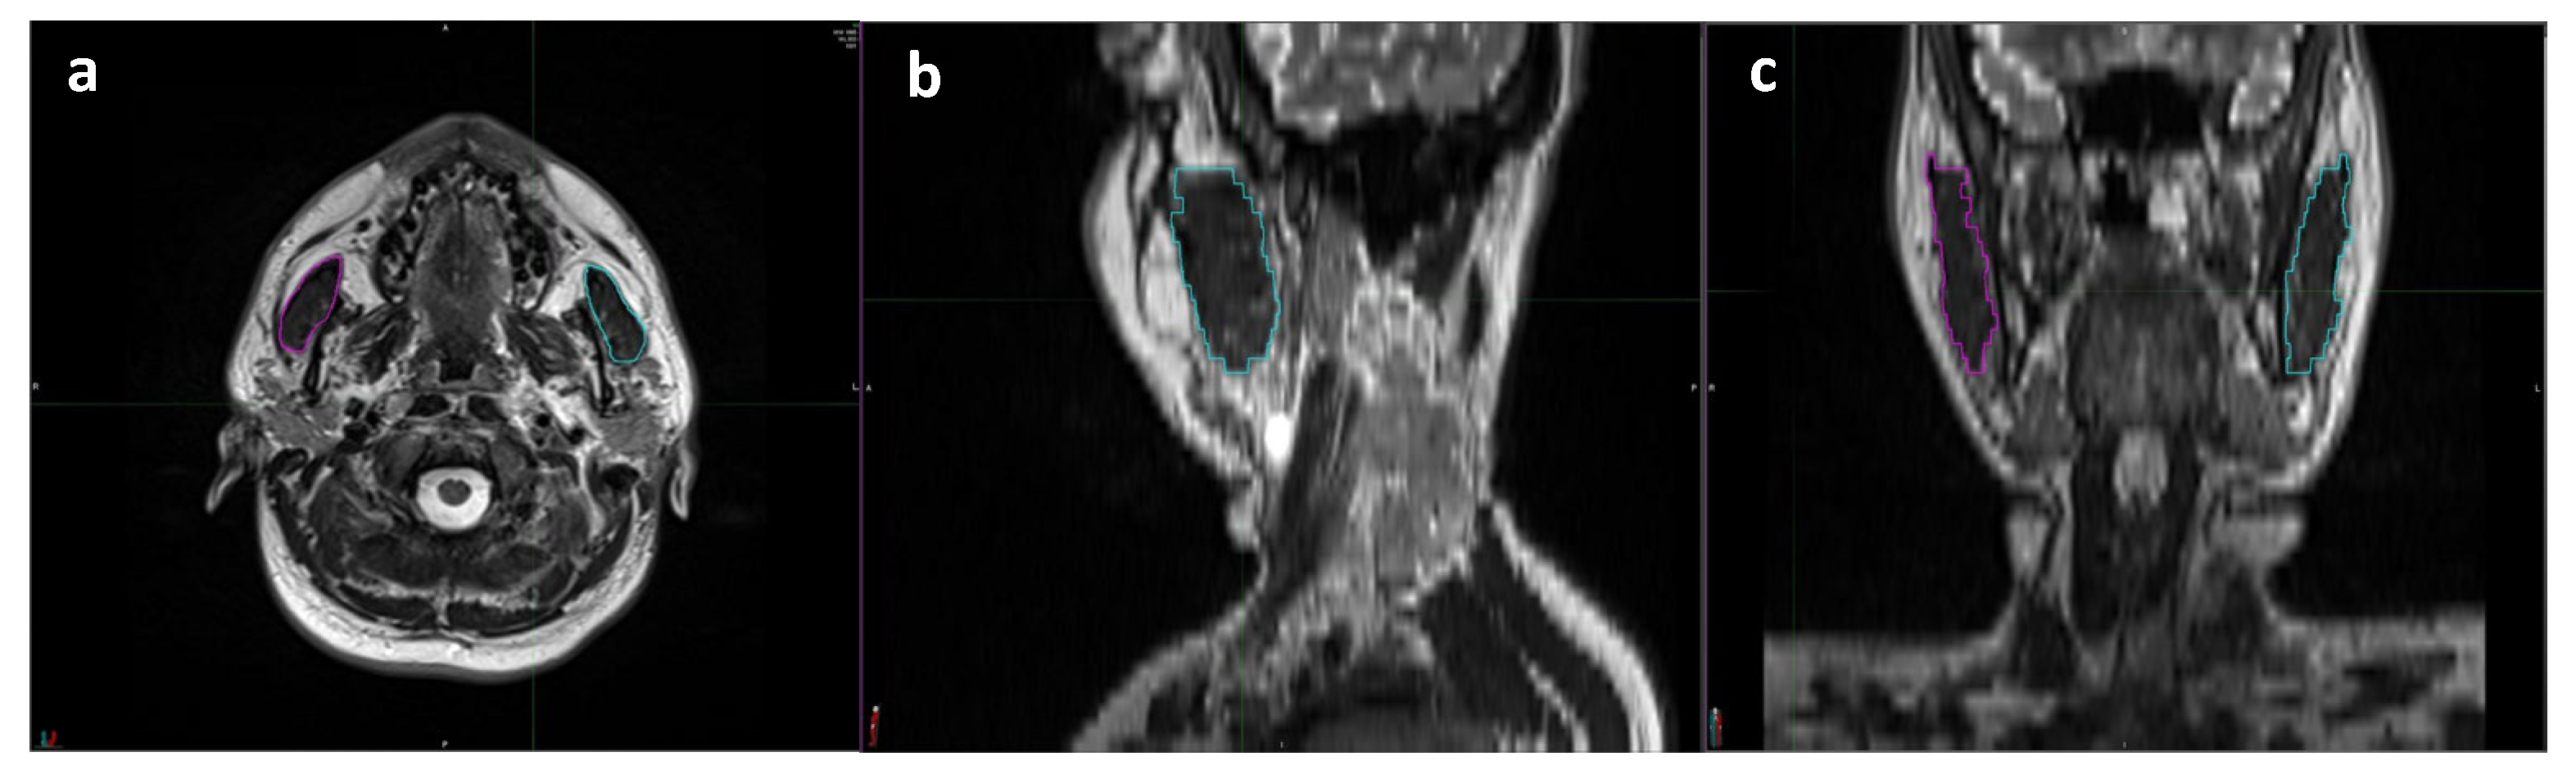

2.4. Baseline Total Masseter Muscle Volume Measurements